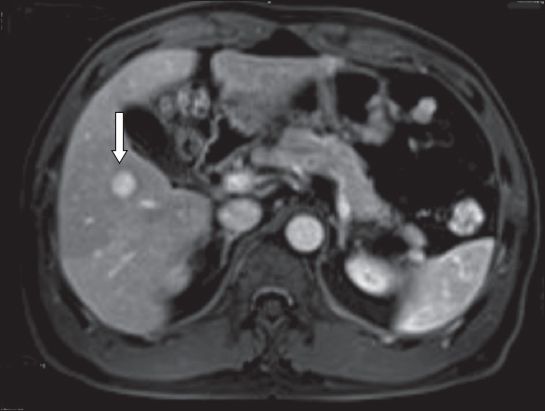

A 53-year-old man with chronic hepatitis B was detected to have a segment V tumour on surveillance ultrasonography. Magnetic resonance (MR) imaging revealed an indeterminate arterial enhancing lesion (measuring 2.1 cm) with atypical washout pattern in the portal venous phase (

Fig. 2

Case 2: MR image of the liver of the patient (who has chronic hepatitis B) shows an indeterminate segment V lesion (arrow).